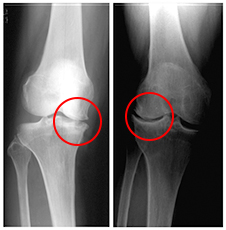

下の画像をご覧ください。

この画像は、整形外科でレントゲン撮影を行い変形性関節症と判断されたものです。

○の部分にご注目ください。

関節軟骨は減り、骨も変形し始めているのが確認できます。

しかし、この時点でお客さんの膝に痛みはありません。

「変形性関節症」 確かにそうです。

画像を見る限り、誰もがそのように判断するのは間違いないでしょう。

だからと言って、骨の変形=痛み、軟骨のすり減り=痛み ではないのです。